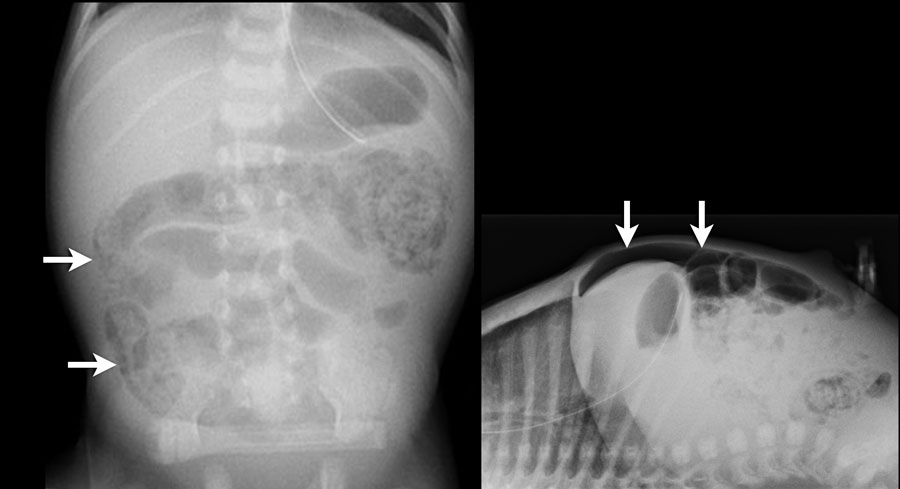

Các hình ảnh cho thấy một trường hợp điển hình của viêm ruột hoại tử với khí trong thành ruột.

Trên hình chụp tia ngang, không có dấu hiệu khí tự do trong ổ bụng.

Đây là một trường hợp điển hình khác của viêm ruột hoại tử.

Lưu ý hình ảnh khí trong tĩnh mạch cửa (mũi tên) và các nhánh tĩnh mạch cửa ngoại vi.

Dấu hiệu này được thấy trên X-quang và siêu âm.

Ở bệnh nhân viêm ruột hoại tử này, hãy chú ý các bóng khí trong thành ruột và trong nhu mô gan.